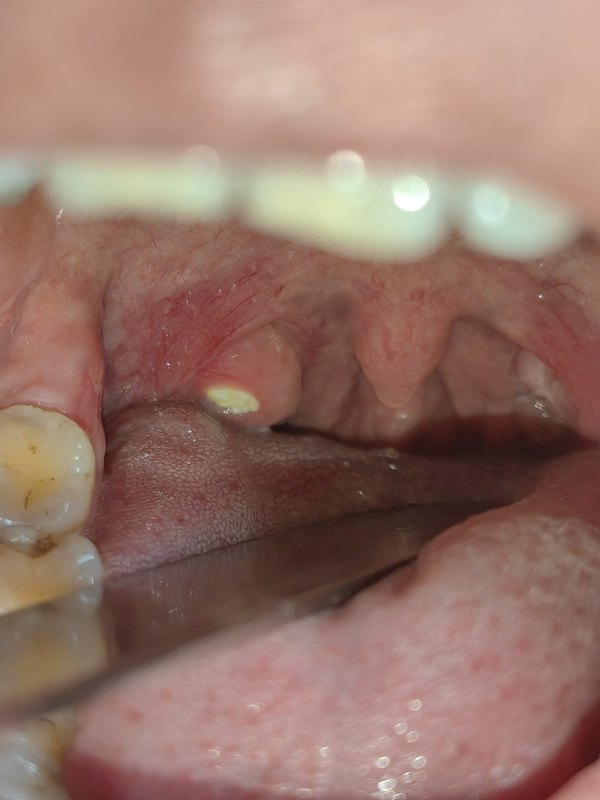

右側(cè)扁桃體中間的白色物為扁桃體結(jié)石(膿性上皮栓)術(shù)后醒來六小時(shí)后,第一餐,如果胃腸可以耐受,最好吃牛奶冰淇淋、雪糕、冷藏的牛奶等冰的流質(zhì)或常溫的牛奶,白粥,蜂蜜水第2餐起可以增加:放涼的或者微溫的:肉片粥,皮蛋瘦肉粥,魚片粥,紅薯粥,蒸水蛋,蒸南瓜,老火湯里面煲過的胡蘿卜、排骨肉、土豆、淮山、雞腿肉,蒸的嫩豆腐,津泡了牛奶或者白粥的戚風(fēng)蛋糕…等類似質(zhì)地的柔軟的半流質(zhì)。第2-7天就可以增加煮的軟爛一點(diǎn)的面、湯河粉、米粉等等。包括很煮的蒸的嫩的很滑的肉片,蒸魚(小心避免卡魚刺)等等都可以吃。7天后,如果咽痛癥狀繼續(xù)減輕,就可以吃比平時(shí)稍軟一點(diǎn)的飯、滑嫩的菜,肉餅……咽痛幾乎完全消失以后就可以正常吃飯了傷口沒有完全恢復(fù)正常之前注意避免的食物:過酸的食物、水果。粘性的食物、水果比如香蕉、糯米糍、年糕。粗糙過硬的食物,比如花生瓜子、麻花等等,纖維太過粗糙的食物比如芹菜、玉米